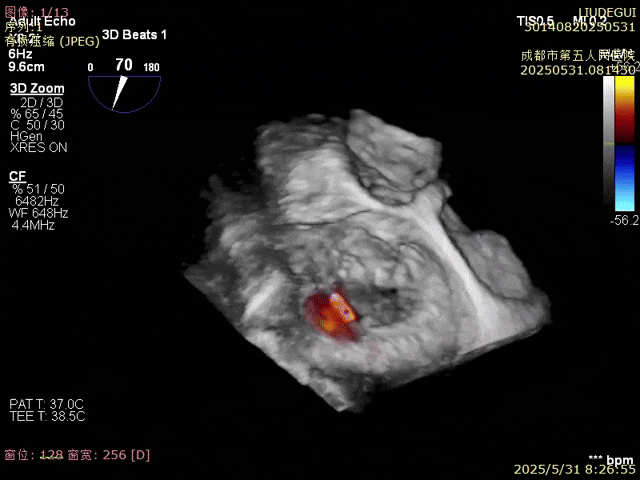

使用二尖瓣夾進行瓣葉捕獲,并進行夾合

確認夾合位置及效果